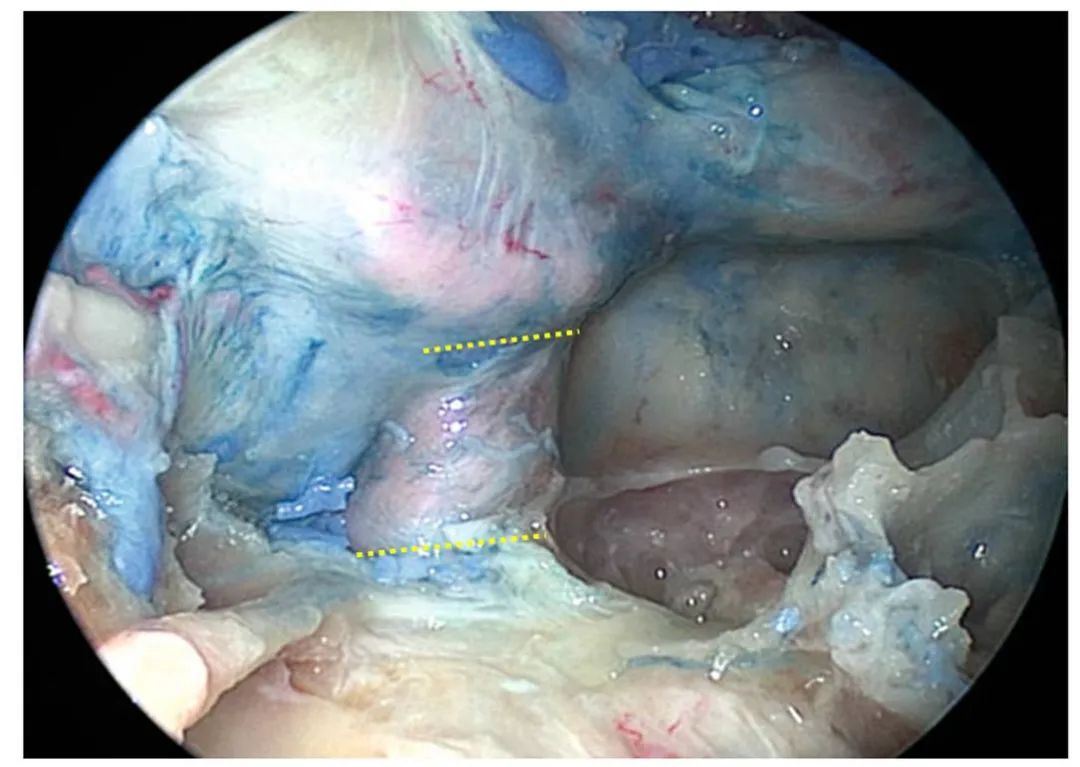

图4. 从鼻-上颌窦径路方向,内镜观察颞下窝。根据卵圆孔,位于翼突外侧板后方、颈内动脉颅底入口前方,进而判定此帧解剖操作行进的位置:从鼻-上颌窦后壁-翼腭窝,在翼腭窝之后,在咽旁颈内动脉之前。内镜为2D观。下牙槽神经、舌神经等,尽管与咽旁颈内动脉出现在同一平面图上,但仍需知道:下颌神经及其分支的后方(深面),为咽旁颈内动脉。从事内镜手术,术者要知深浅,始终知道深面的结构是什么,这样才有利于重要结构的保护。手术的过程,应是不断印证预见的过程。